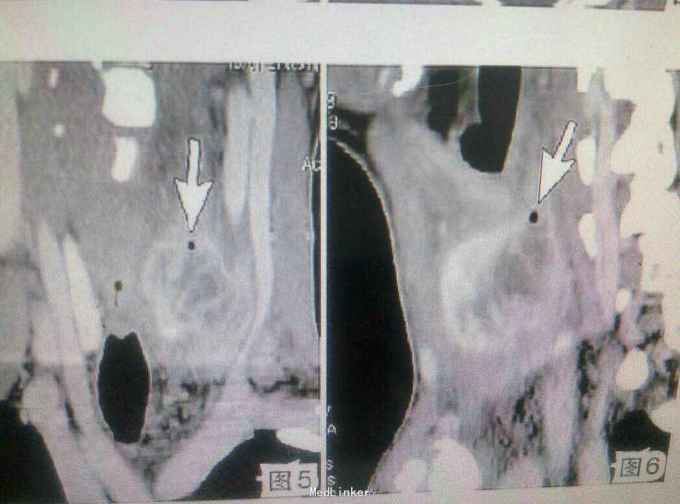

查体:气管右移,颈前区偏左可触及一约3.1cm×2.0cm大小肿物,质韧,表面光滑,边界清楚,活动度好,有压痛,有囊性感,可随吞咽上下活动。 辅查:超声检查:甲状腺左叶内低回声结节,周界清,内少许无回声区,诊断甲状腺腺瘤囊性变。 影像学诊断:甲状腺脓肿

随访与讨论:患者经手术及抗炎治疗后患者恢复良好,痊愈出院。 甲状腺脓肿少见,临床多有局部皮肤红肿疼痛,有压痛,可提示诊断;临床表现不典型时诊断困难;影像学检查发现病变内气体是正确诊断的主要依据,薄层高空间分辨率CT影像显示微小气泡的敏感度高、特异性好,是诊断甲状腺脓肿的重要方法。甲状腺脓肿常由化脓性细菌引起,临床表现为甲状腺局部红、肿、热、痛,常伴有全身中毒症状。 实验室检查见血白细胞数增高,临床根据其典型症状及体征即可做出诊断。CT是诊断甲状腺疾病十分有效的检查方法。 治疗:1.脓肿穿刺;通过穿刺把脓液抽出,消炎抗菌治疗。 2.手术治疗,主要也是对脓肿病灶进行脓液清除,设置引流,对症抗菌消炎。